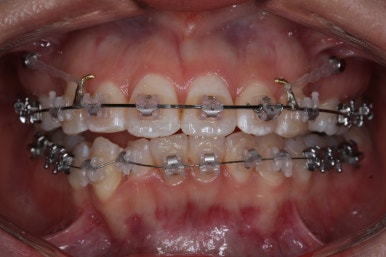

틈은 다 다물어졌고, 부가적인 정교한 마무리 과정을 더 거치게 됩니다.

중앙선도 잘 맞고 교합도 잘 마무리되었습니다.

이 뽑은 자리가 다시 벌어지지 않게 앞니가 다시 틀어지지 않게 유지철사를 부착하고 마무리를 하였습니다.

전후 비교해 보겠습니다.

중앙선, 교합, 뻐드러짐 모두 좋아졌고 이를 뽑고 교정했지만 발치 공간이 남지 않고 잘 마무리 되었습니다.